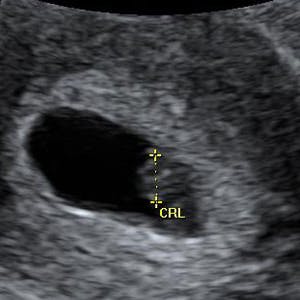

Gravid

Vi gør en dyd ud af at klæde dig godt på både før, under og efter din graviditet. Vi ved, at der kan komme mange spørgsmål til din graviditet, fødsel, amning, din babys udvikling og mange flere emner, derfor har vi samlet guides, tips & tricks samt læsernes egne fortællinger i dette gravid univers.